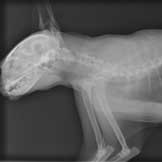

Their tone became solemn as they described how Trixie had developed a slight cough over the past few weeks, which did not resolve with treatment with antibiotics and anti-inflammatory medications. Her primary veterinarian performed radiographs (X-rays) of her chest the week before their appointment with me and saw a suspicious area within the cranial (front) part of her chest cavity. She was very worried about a tumor as a cause of the chronic cough, and so she referred Trixie and her owners to the oncology service at my hospital for further testing and treatment options.

Prior to meeting with Trixie’s owners, I reviewed her radiographs and saw exactly what her veterinarian was troubled about. I too was concerned about what I saw on the films. There was an irregular mass located in the normally tiny space between the left and right topmost portion of Trixie’s lungs, sitting just in front of her heart. From a purely logical standpoint, the odds weren’t in Trixie’s favor. She was a geriatric cat, and some statistics suggest that more than 50 percent of pets over the age of ten will develop cancer.

Image: Emma’s Xray by Jason Pierce / via Flickr